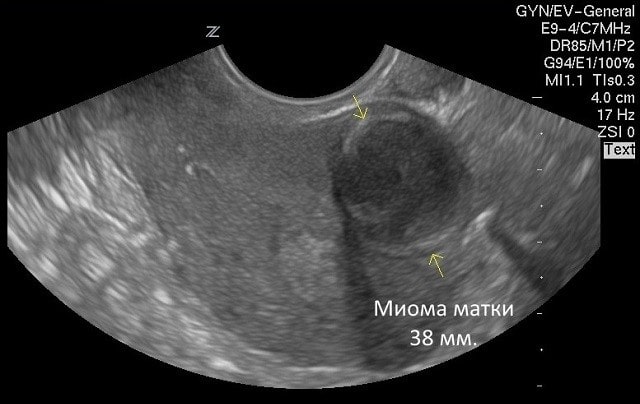

Миома матки – это образование доброкачественное, сформированное из двух типов ткани: из соединительной – фибромиома, из мышечной – лейомиома. Это может быть маленький едва заметный узел или такой большой, что кажется, будто женщина беременна. Если образование маленькое и не доставляет беспокойств, оно случайно обнаруживается при плановом УЗИ.

Также миомы матки бывают межсвязочными и паразитарными. УЗИ или другие виды диагностики помогают определить место расположения узлов и направление роста.

Диагностировать миому может только врач. Он выяснит симптоматику, осмотрит женщину, проведет УЗИ или другие процедуры, при необходимости назначит анализы. Затем он подберет подходящее лечение.